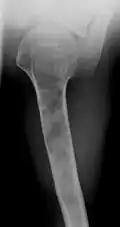

X-ray showing enchondromas localized in the humerus of a 37-year-old patient affected with Ollier disease -

X-ray showing enchondromas localized in the lower part of the radius of a 37-year-old patient affected with Ollier disease -

Abnormal bone growth such as shortening or thickening and deformity may be observed in patients of Ollier disease. These bone lesions are visible at birth using radiography but are usually not screened or examined for until clinical manifestations present during early childhood. However, some patients may exhibit no signs of any symptoms.[1] One study found thirteen to be the mean age of diagnosis in patients with Ollier disease. In an X-ray, there would normally be the presence of several homogeneous lesions of an oval or elongated shape with bone edges that are slightly thickened.[3] With age, these lesions may calcify and appear as diffusely minute spots or stippled. Fan-like septations or streaks would be indicative of the presence of several enchondromas. Early detection and consistent and repeated monitoring is important in order to prevent and treat any potential bone neoplasms.